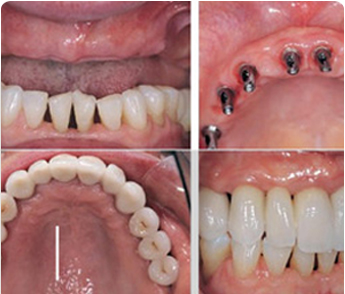

当天种植,

当天即可戴牙

全口植入8颗

半口植入4颗

突出特点,实现即拔即种即用,结合后能吃能咬

可以解决全口、半口无牙颌、 牙槽骨严重萎缩/极薄问题。

ICX种拥有很高的灵活性,面对长期半颌和全颌重度骨缺损也能理想修复。ICX全颌新的multi全颌修复方案,在短短的1-2小时内即可完成手术,避免了长期复杂的骨移植手术,大大减少了手术创伤,节省了治疗费用。